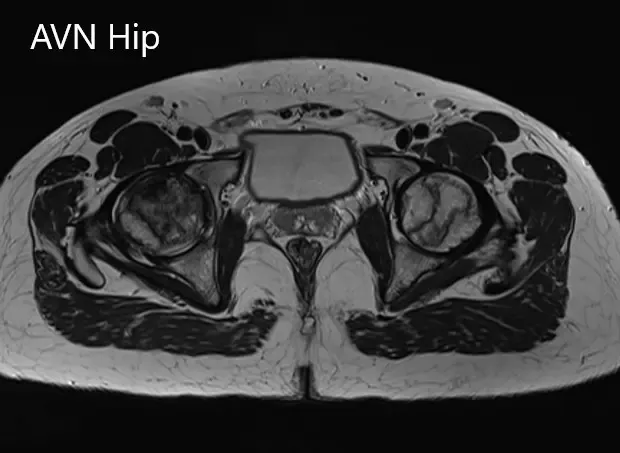

Sección coronal T1WI de la resonancia magnética que muestra AVN en cadera.

Sección coronal T2WI de la resonancia magnética que muestra AVN de cadera.

Secciones axiales de la T2WI y T1WI de la MRI.

Había zonas hipointensas tanto en T1WI como T2WI en ambas cabezas del fémur, sugestivas de esclerosis. Había edema de médula ósea circundante y la zona necrótica bilateral era aproximadamente del 70%.